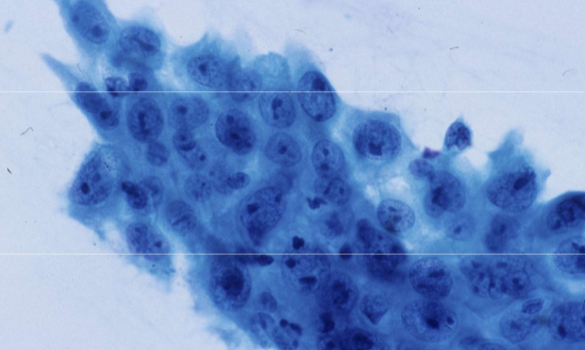

adenocarcinoma